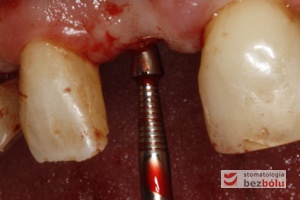

Wprowadzenie implantu do łoża – implant Ankylos wprowadzany ręcznie przy użyciu raczety

Wprowadzanie implantu w pozycji kła – ręczne wprowadzanie implantu daje możliwość kontroli torku i regulowania tempa implantacji